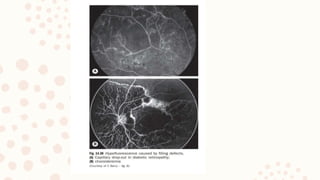

9.FLUORESCEIN ANGIOGRAPHY

FFA is a very useful tool in diagnosing macular disorders

– e.g. diabetic maculopathy, CSR and can reveal the functionality of the lesion